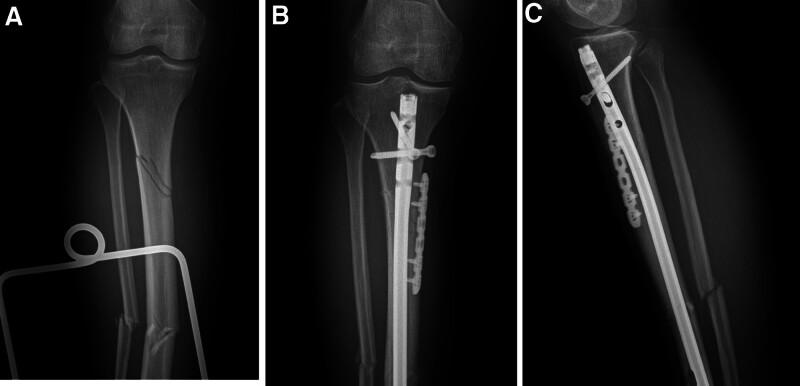

It is unclear whether small plates are needed for augment fixation to provide a more stable mechanical environment in segmental fractures of the tibia treated with intramedullary nail. The purpose of this study was to investigate the efficacy of intramedullary nailing combined with locking plates in the treatment of segmental fractures of the tibia. This study included 41 patients with segmental tibia fractures between January 1, 2018 and January 1, 2023. Eighteen patients were treated with an intramedullary nail assisted by a locking plate (combination group), and 23 patients were treated with an intramedullary nail without a plate (nail group). The perioperative parameters of all patients were recorded, and clinical efficacy was evaluated during follow-up. The operation time was shorter but the incision was longer in the combination group (P < .05). The numbers of fluoroscopy procedures and the time to union were shorter in the combination group (P < .05). The rate of malunion in the nail group (4, 17.4%) was significantly greater than that in the combination group (0, 0%). At the last follow-up, no statistically significant differences in walking ability were detected. Our results suggest that a locking plate combined with an intramedullary nail for segmental tibial fractures may require a longer surgical incision, but it has significant advantages such as a shorter operative time and time to union, a shorter fluoroscopy time, and a lower rate of malunion and nonunion. Intramedullary nail fixation assisted by a locking plate is an effective method for treating segmental fractures of the tibia.

对于在使用髓内钉治疗的胫骨节段性骨折中,是否需要小钢板进行增强固定以提供更稳定的力学环境尚不清楚。本研究的目的是探讨髓内钉联合锁定钢板治疗胫骨节段性骨折的疗效。本研究纳入了2018年1月1日至2023年1月1日期间的41例胫骨节段性骨折患者。18例患者采用锁定钢板辅助髓内钉治疗(联合组),23例患者采用无钢板髓内钉治疗(髓内钉组)。记录所有患者的围手术期参数,并在随访期间评估临床疗效。联合组手术时间较短但切口较长(P < 0.05)。联合组的透视次数和骨折愈合时间较短(P < 0.05)。髓内钉组的畸形愈合率(4例,17.4%)显著高于联合组(0例,0%)。在最后一次随访时,未检测到步行能力的统计学显著差异。我们的结果表明,锁定钢板联合髓内钉治疗胫骨节段性骨折可能需要更长的手术切口,但具有手术时间和骨折愈合时间短、透视时间短以及畸形愈合和不愈合率低等显著优势。锁定钢板辅助髓内钉固定是治疗胫骨节段性骨折的有效方法。